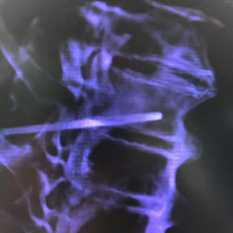

(Справа) КТ, сагиттальная проекция, костный режим с переформатированием: подтверждается наличие плотного склерозированного костного островка с неровными щетко-образными краями. Также обратите внимание на то, что патологический очаг расположен вдоль длинной оси тела позвонка. Костный островок может иметь округлую или овальную форму. В этом случае это единственно возможный обоснованный диагноз. (Слева) МРТ, сагиттальная проекция, режим STIR: небольшая отчетливо визуализирующаяся зона сигнала низкой интенсивности в теле позвонка. Сигнал сохраняет низкую интенсивность во всех последовательностях. Обратите внимание на отсутствие в режиме STIR перифокального отека или реактивных изменений.

(Справа) МРТ, сагиттальная проекция, режим Т1, с контрастным усилением: у этого же пациента отсутствуют признаки контрастного усиления патологического очага, что подтверждает диагноз костного островка. Если рентгенография не позволяет достоверно дифференцировать костный островок и метастаз, исследование с контрастным веществом помогает снять все вопросы.